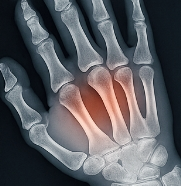

관절염에 좋은 음식 관절염이란?

관절염은 관절 부위에 염증이 생겨 통증, 뻣뻣함, 운동 제한을 유발하는 질환입니다. 특히 퇴행성 관절염(골관절염)과 류마티스 관절염이 대표적인 유형입니다. 다양한 원인으로 관절이 손상되면서 증상이 나타나며, 관절염에 좋은 음식을 통한 관리가 중요한 이유도 여기에 있습니다.